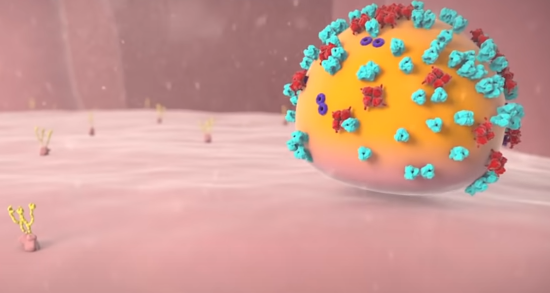

这些抗体会识别并结合之前提到的刺突糖蛋白,防止病毒仿制出可以打开细胞大门的钥匙。

另外,这些抗体会将病毒黏连在一起,同时通知免疫细胞中的吞噬细胞来摧毁病毒,避免它在体内蔓延。

最终,病毒的攻势会在免疫系统的积极应对下,土崩瓦解。

战胜新冠病毒的康复者血液中,在短时间内会储备大量的抗体避免病毒反扑,这些抗体是目前为止针对病毒的最有效的武器。因此在《新型冠状病毒感染的肺炎诊疗方案(试行第七版)》中提到 “康复者血浆治疗” 可以用于病情进展较快、重型和危重型患者。